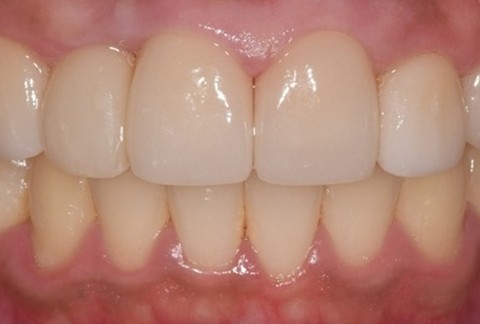

임플란트-보철-시-기성-어버트먼트가-아닌-맞춤-지대주-사용-보철-파절-위험-방지-음식물-끼임-방지-주위염-방지-맞춤-지대주는-환자의-구강환경에-맞는-교합을-구현할-수-있고-앞니-보철시-더욱-심미적으로-제작이-가능합니다

임플란트-전후사진